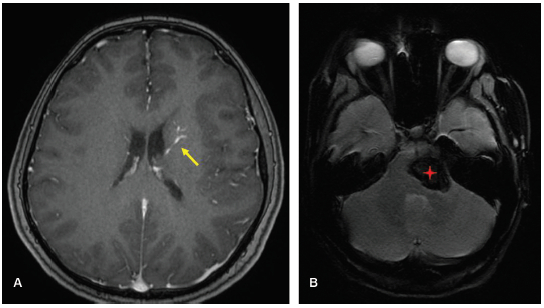

En la RM sin contraste endovenoso pueden pasar desapercibidos, evidenciándose únicamente la vena central dilatada como un vacío de flujo lineal. Las secuencias ponderadas en T2 pueden mostrar alta intensidad de señal debido al flujo lento de tipo venoso, que no debe confundirse con trombosis. Con frecuencia, en estas secuencias se observa una línea paralela de alta señal rodeando la vena colectora, que probablemente corresponda a un espacio perivascular con LCR. Con la administración del contraste realza intensamente y puede apreciarse la imagen típica en cabeza de Medusa.5 Adicionalmente, las imágenes de susceptibilidad magnética (SWI, por su sigla en inglés), como el T2 , pueden mostrar focos hipointensos si se asocian a hemorragia o a malformación cavernosa (►Figura 3).1,5

Son más frecuentes en las regiones irrigadas por la arteria cerebral media y en el territorio de la vena de Galeno, y pueden estar asociados a una malformación cavernosa en un 30% de los casos. No son hereditarios.2,3